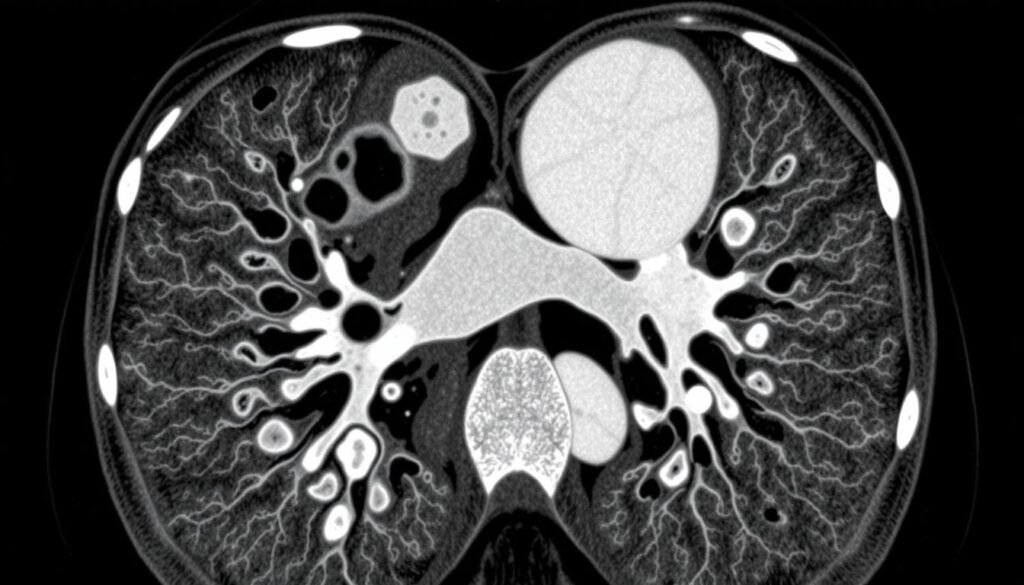

Small Cell Lung Cancer CT Scan

CT scans are crucial for diagnosing SCLC. They let doctors see unusual masses in the lungs. They also check for cancer spread to lymph nodes and nearby areas. An initial small cell lung cancer CT scan with contrast is standard. This makes the scan clearer.

How CT Scans are Used in Diagnosing SCLC

CT scans are key in spotting SCLC early. Each year, about 34,000 people in the U.S. find out they have SCLC. Sadly, most are already in the late stages. Early stages are rare, making up just 10.5% of cases. This situation underscores the need for better imaging to catch cancer early. Low-dose CT scans are especially hopeful, catching cancer early 76.5% of the time. Early detection helps doctors tailor treatment better. For more on imaging’s role, see this resource.

CT Scan and Staging of SCLC

Staging SCLC accurately is vital for choosing the right treatment quickly. CT scans are good at showing if the disease is limited or widespread. This helps doctors make important treatment choices. Plus, PET/CT scans bring even more precision, pointing out cancer spread to places like the liver and brain. With most SCLC found late, imaging’s role is clear. It guides oncologists in planning the best treatment path. For more on how diagnostics work, look at this guide.